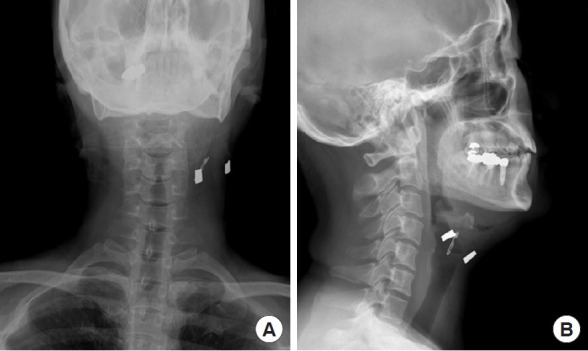

吸脂术是一种广泛应用于各种目的的美容整形手术。先进吸脂技术的使用降低了并发症的风险。然而,它们仍然会意外地发生。在此,我们报告一个罕见的情况下,一个44岁的病人谁经历了一个破裂的套管尖端卡在她的颈部颈面抽脂。该病例强调了通过严格的术前设备检查和适当的仪器维护来预防此类并发症的必要性。此外,当试图去除破损的器械尖端时,在手术前和手术过程中进行影像学检查以精确定位和提取碎片,确保患者安全和成功的结果是至关重要的。

Liposuction is a widely performed aesthetic plastic surgery procedure used for various purposes. The use of advanced liposuction techniques has reduced the risk of complications. Nevertheless, they can still occur unexpectedly. Herein, we report a rare case of a 44-year-old patient who experienced a broken cannula tip lodged in her neck during cervicofacial liposuction. This case highlights the need for vigilance in preventing such complications through rigorous preoperative equipment inspections and proper instrument maintenance. Additionally, when attempting to remove a broken instrument tip, it is crucial to perform imaging examinations both before and during the procedure to precisely locate and extract the fragments, ensuring patient safety and a successful outcome.